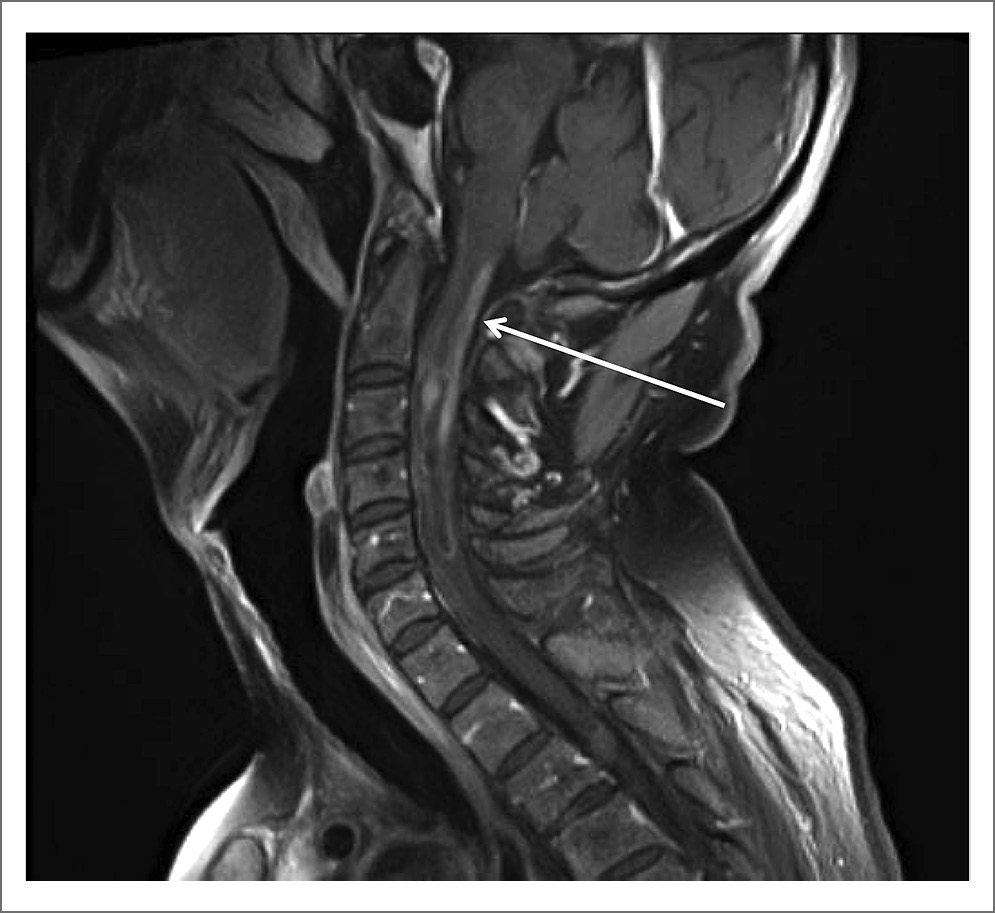

Для уточнения диагноза провели МРТ ГМ и спинного мозга. При исследовании ГМ отмечены единичные мелкие очаги в белом веществе и небольшие зоны лейкоареоза, отражающие микроангиопатию. МРТ-исследование спинного мозга в режимах T2-взвешенного изображения и FLAIR выявило протяженные участки повышенного МР-сигнала (на уровне шести шейных позвонков), заметное утолщение и неоднородную структуру шейного отдела спинного мозга, вероятно, воспалительного генеза (рис. 1, 2). При внутривенном контрастном усилении определялось накопление контрастного вещества в левом зрительном нерве на всем его протяжении (рис. 3) и в белом веществе спинного мозга, преимущественно в области задних столбов с переходом на нижнезадние отделы продолговатого мозга – зона аrea postrema (рис. 4).

Рис. 3. Накопление контрастного вещества в левом зрительном нерве (показано стрелками).

Оптический неврит при ОНМ может быть как с выраженным и стойким нарушением зрения [10], так и асимптомным, патология которого выявляется только специальными методами исследования [1]. У нашего пациента расстройства зрения были выраженными без каких-либо характерных изменений при офтальмоскопии, и только МРТ с контрастированием позволило остановиться на воспалительном характере поражения зрительного нерва (рис. 3).